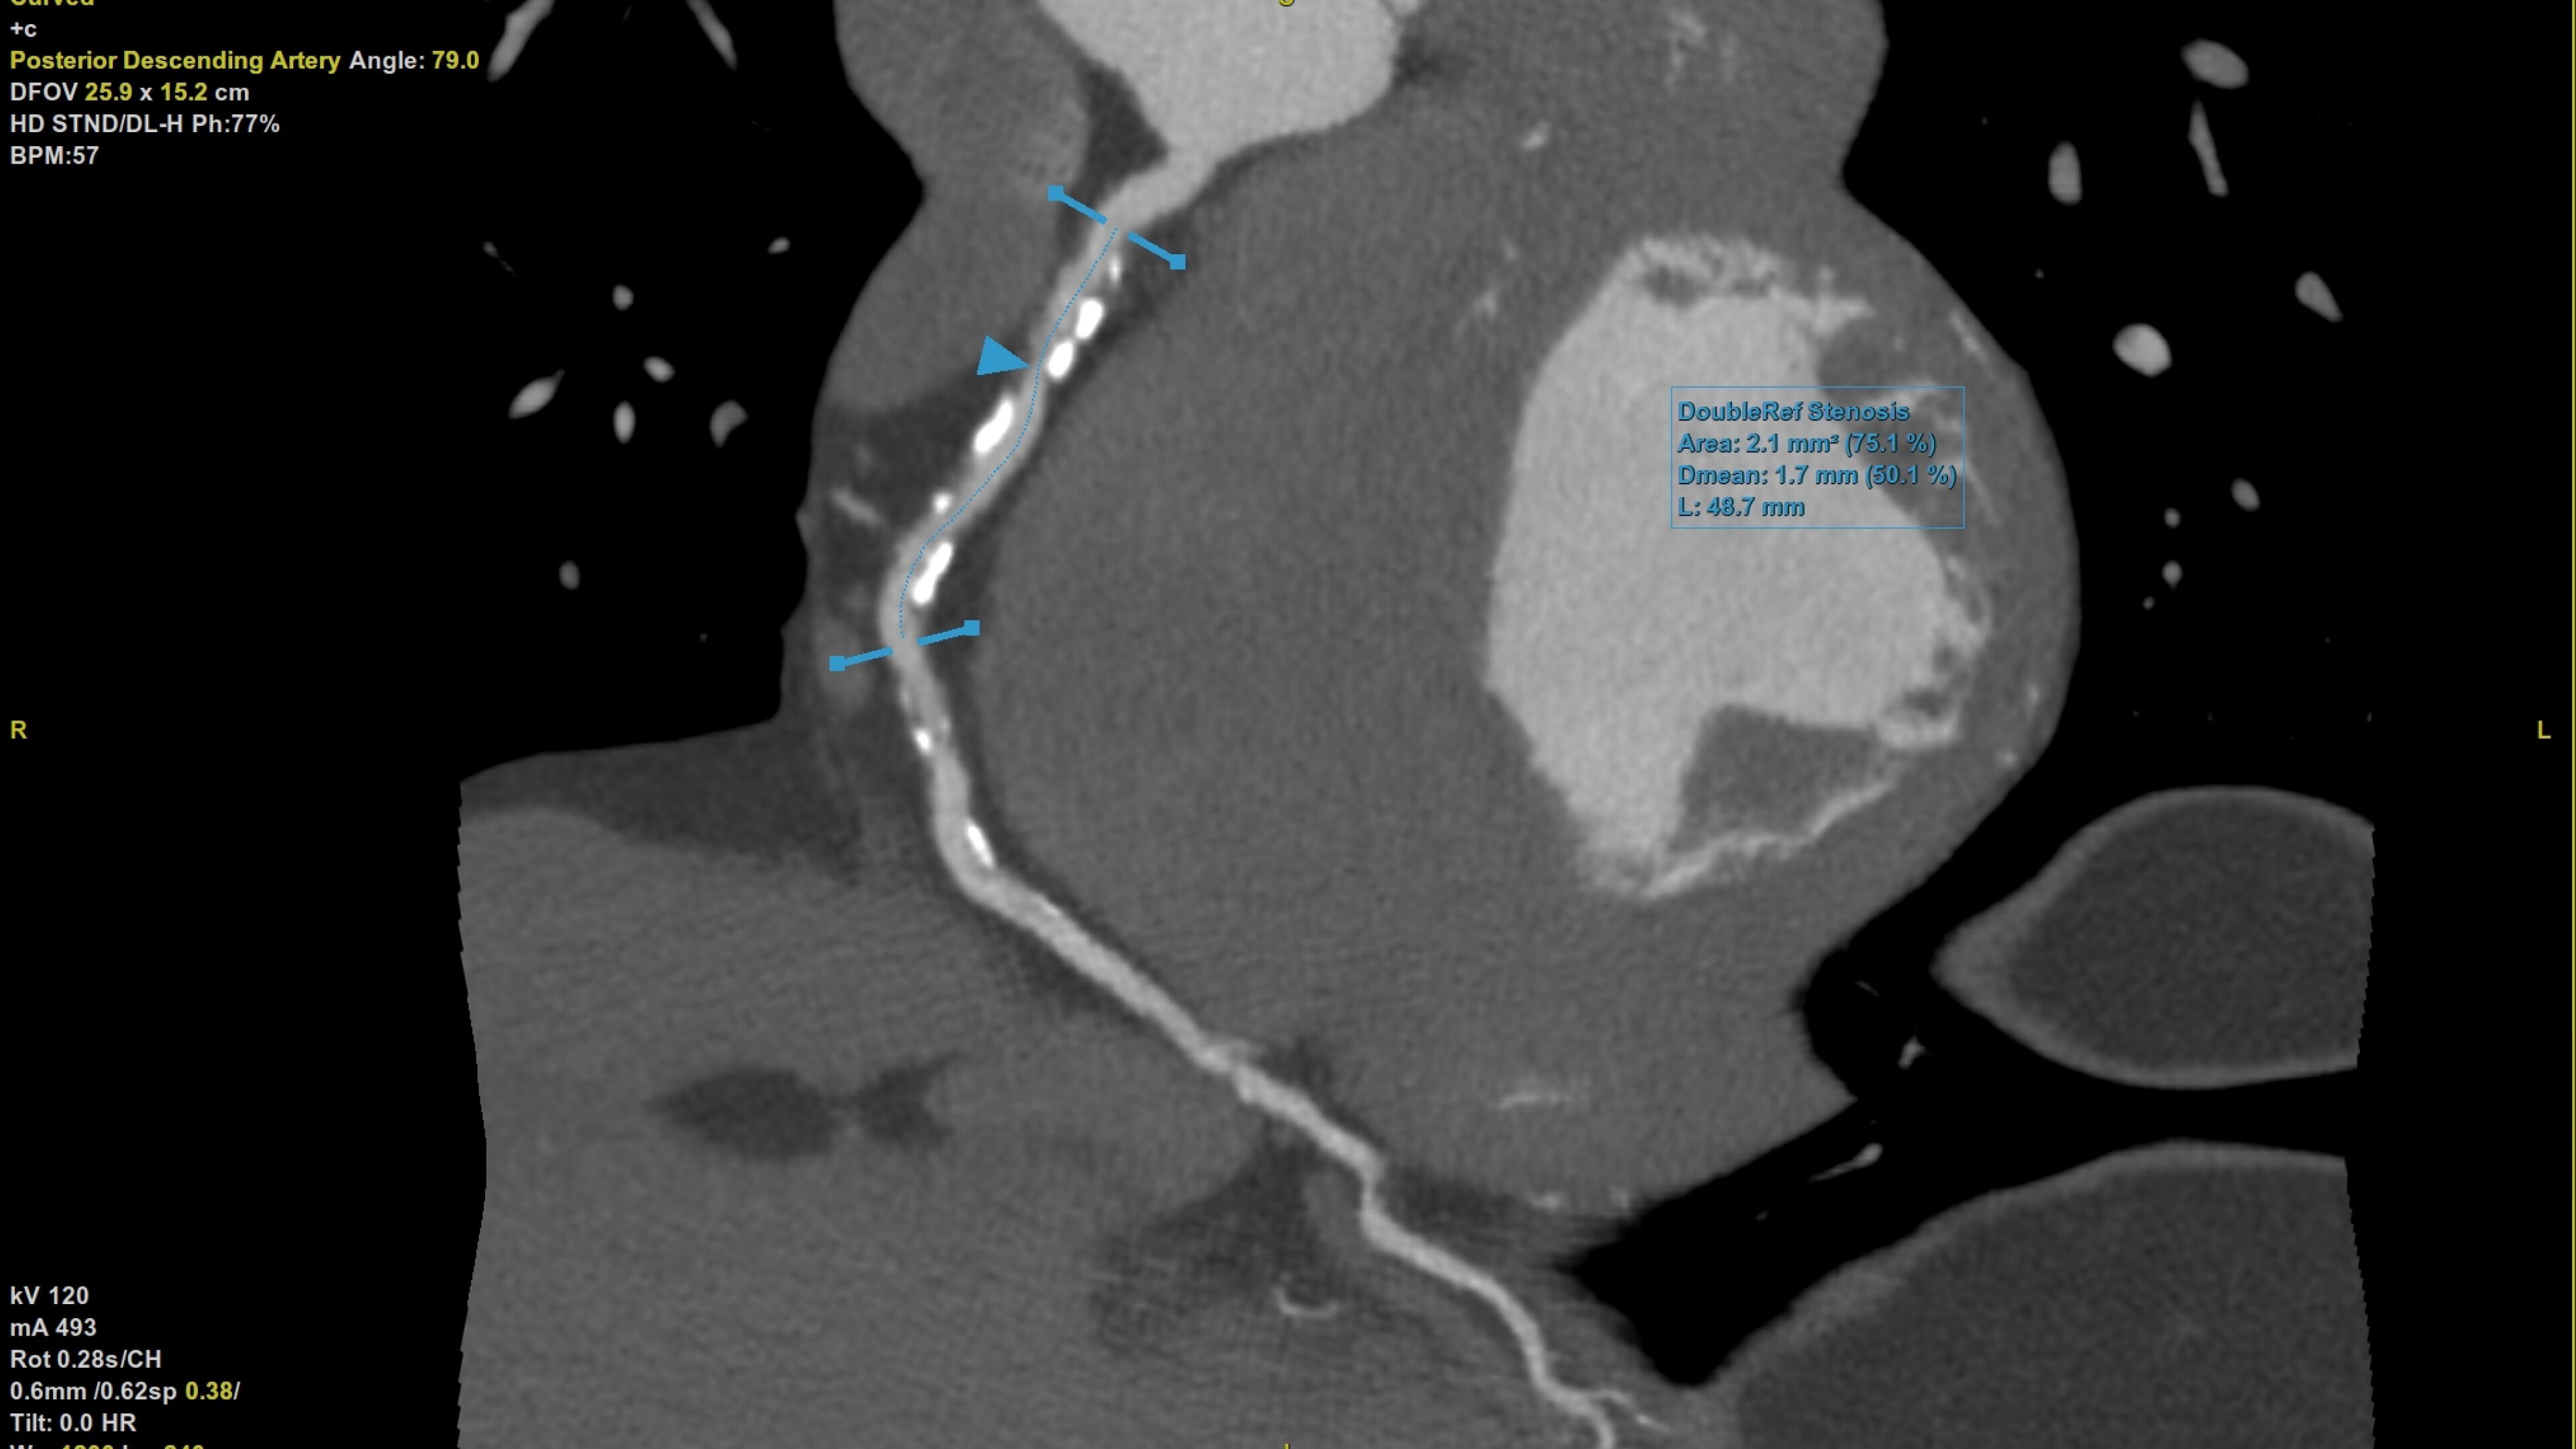

Plaque ID tool assists in visualizing and quantifying plaque burden

• Plaque ID provides volume measurements for four distinct Hounsfield ranges to aid with identification and visualization of coronary plaque